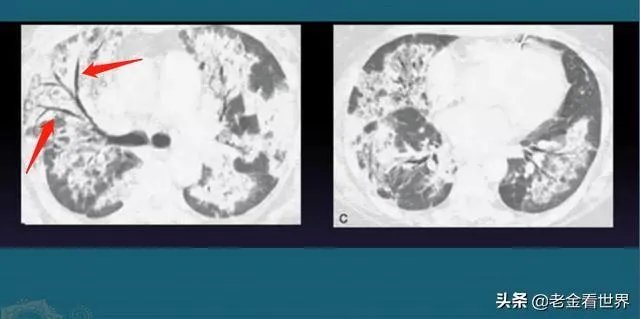

随后美国马里兰州的周围几个州开始流行一种不明原因的白肺病,患者肺部发白,这个症状和新冠肺炎的症状一模一样!美国医管局解释这是电子烟造成的,并且禁售电子烟;事后科研工作者做了多次试验,并不能证明电子烟对肺部能造成白肺;

既然美国疾控中心主任承认了流感疫情中有新冠肺炎,而新冠肺炎不是天上掉下来的,最接近新冠肺炎特征的就是白肺病,由此可以推断,白肺病就是去年8月开始流行的新冠肺炎!